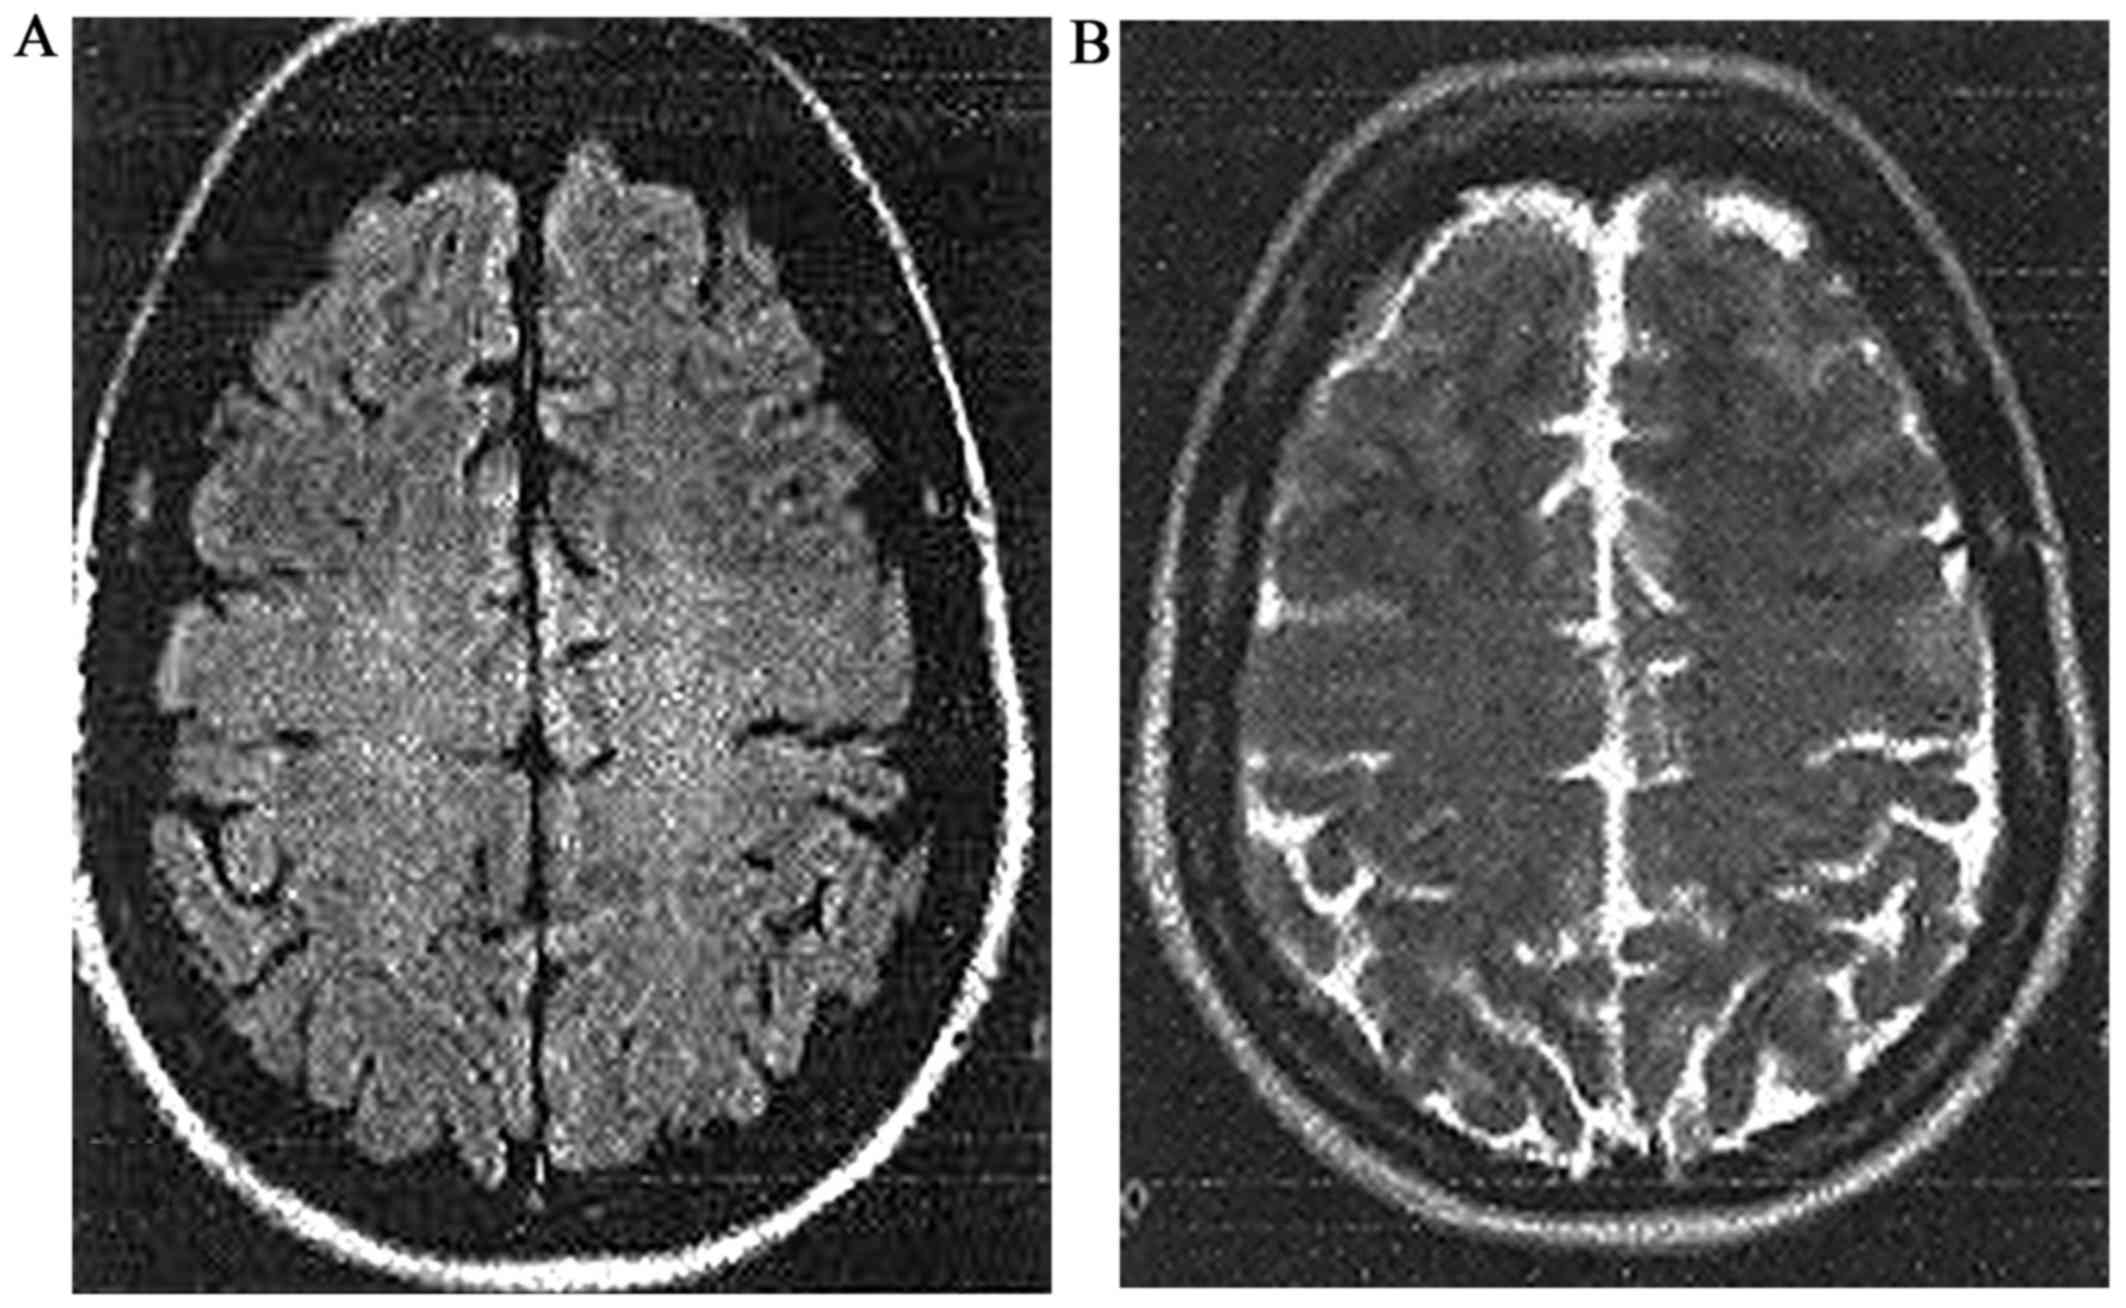

On examination, 11 weeks from the last dose of mitomycin C, the patient was pale, afebrile, tachypneic, and tachycardic, with signs of bilateral pleural effusion, hepatomegaly, pitting edema, hypertension of 240/120 mmHg, and a grade II hypertensive retinopathy. Blood tests showed hemolytic anemia with 9 g/dl Hg (12–16 g/dl), accompanied by lactic acid dehydrogenase (LDH) of 6,400 u/l (240–480 U/l), total bilirubin of 28 µmol/l (0–17 µmol/l), and thrombocytopenia of 45 10e9/l (140-40010e9/l), with numerous schistocytes on peripheral blood smear. She also had acute renal failure with creatinine of 309 µmol/l (46–92 µmol/l) and blood urea nitrogen (BUN) 17 mmol/l (0–8.3 mmol/l). Activity levels of ADAMTS13 (a disintegrin and metalloproteinase with thrombospondin type 1 motives) activity levels were normal. This combination and the previous maximal mitomycin-C dose was consistent with the diagnosis of TMA induced by mitomycin-C (11,15). Despite maximal antihypertensive treatment, the patient's blood pressure remained uncontrolled and she became acutely confused with cortical visual deficit and generalized tonic-clonic seizures that responded to intravenous phenytoin. Brain MRI demonstrated extensive hyperintense posterior white matter lesions on T2 and T2/fluid-attenuated inversion recovery (FLAIR) weighted images typical of PRES (Fig. 1).

Figure 1.

Admission brain MRI of patient 1: Admission brain MRI in a 36-year-old woman with posterior reversible encephalopathy syndrome (PRES) following mitomycin-C (cumulative dose 57 mg/m2. The MRI is 11 weeks after the last dose) for the management of her metastatic colon cancer. The findings are suggestive of posterior reversible encephalopathy syndrome (PRES). (A) Axial T2-weighted fluid-attenuated inversion recovery (FLAIR) and (B) T2-weighted images revealed multiple hypertintense posterior white matter lesions. A scanned version of the images that were prepared many years ago.